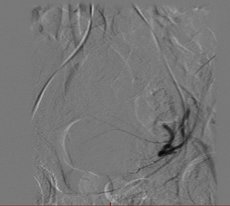

Bei der Embolisation wird über die Leiste ein sehr dünner Schlauch (Katheter) in die Arterie eingeführt und unter Röntgenkontrolle von einem spezialisierten Radiologen bis zur Gebärmutterarterie vorgebracht. Dort werden feinste Kügelchen (Microsphären) in die Myome gespritzt, so dass diese absterben und die Beschwerden verschwinden. Die Gebärmutter selbst bleibt erhalten.